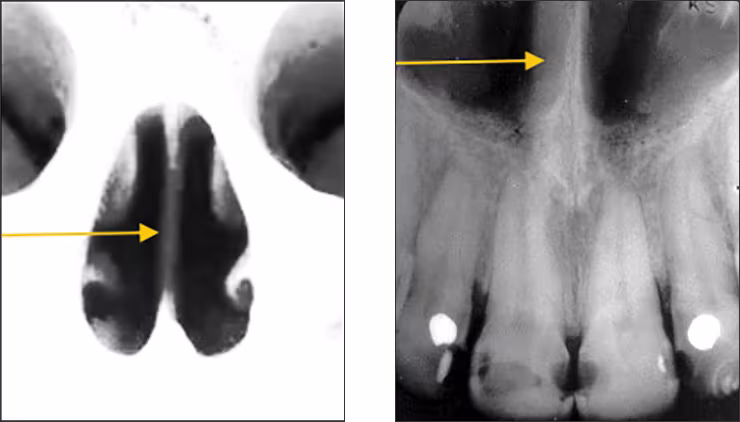

Nasal fossae – The nasal fossae (plural; singular - fossa) are the nasal openings located above the maxillary anterior teeth. The fossae are divided in the midline into right and left chambers. Radiographically, the nasal fossae appear as vertically oblong radiolucent structures bounded by bone. These structures can be seen on maxillary central incisor periapical views and partially on lateral incisor and canine periapical images.

Nasal septum – The nasal septum is a bony vertical band-like midline structure that divides the nasal cavity into right and left chambers. The nasal septum is a radiopaque landmark visible on maxillary central incisor periapical images.

Anterior nasal spine – The anterior nasal spine (ANS) is a bony projection located at the base of the nasal septum in the maxillary midline. Radiographically, the ANS appears as a V-shaped or triangular point radiopacity. This structure is recorded on maxillary central incisor periapical images.

Inferior nasal concha – The inferior nasal concha or turbinate bone projects into the inferior aspect of the nasal fossa from the lateral walls of the nasal cavity. These bilateral radiopaque structures (conchae) are sometimes visible on central and lateral incisor periapical images.

Mid-palatine suture – The mid-palatine suture is the interface of the two halves of the premaxilla where they come together in the midline. The mid-palatine suture is also referred to as the median palatal suture. It courses from the alveolar crest through the midline to the posterior aspect of the hard palate. This structure appears radiographically as a thin vertical linear radiolucency in the midline on maxillary central incisor periapical images.

Incisive foramen – The incisive or nasopalatine foramen is located in the midline on the lingual aspect of the hard palate above the central incisor teeth crowns. The foramen is the termination of the nasopalatine canal. Radiographically, it appears between the roots of the central incisor teeth as a round to oval radiolucency less than one centimeter in diameter. It has a range of sizes and shapes, so variation is not unusual. This structure is recorded on maxillary central incisor periapical images.